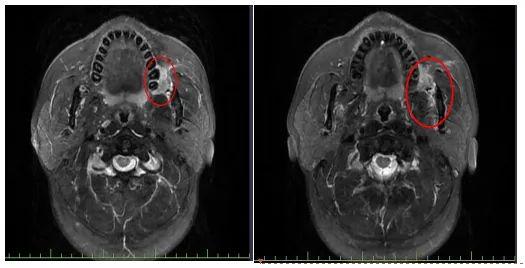

这时,朱大哥脸颊内侧的“溃烂”已经长得像樱桃水果一样大,表面有弹坑,摸起来很硬。核磁共振的结果也说明他左颊有一个肿块,靠近左上颌骨。虽然朱大哥一直不敢相信他怎么会被肿瘤缠住而没有太大的不良反应,但进一步的病理检查结果残酷地表明,左颊高分化鳞状细胞癌。

医院供图